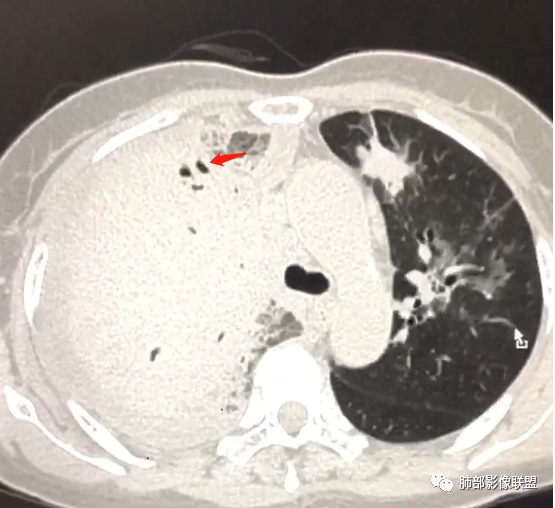

第二次CT:

中老年女性,急性病史,全身症状,提示全身多部位受累。5,29:右肺大量胸水压迫,导致肺叶不张夹杂其中,无法观察病灶实质;左肺病灶沿支气管血管束走向,无叶段性分布,提示间质为主病变。

10天后:胸水减少,右肺病变较前增大,内部未见坏死,含气支气管通畅。

下叶病变明显沿血管束分布

大叶性肺炎、无坏死空洞、间质为主,沿支气管血管束分布,伴随胸水。

常规鉴别:鹦鹉热、肺链、军团、腺病毒、结核。肺链、军团——肺泡性为主,应该外围胸膜下起源,不支持。

结核:无树芽征,内部无坏死,支气管无扩张等,急性病史,不支持。

倾向于鹦鹉热